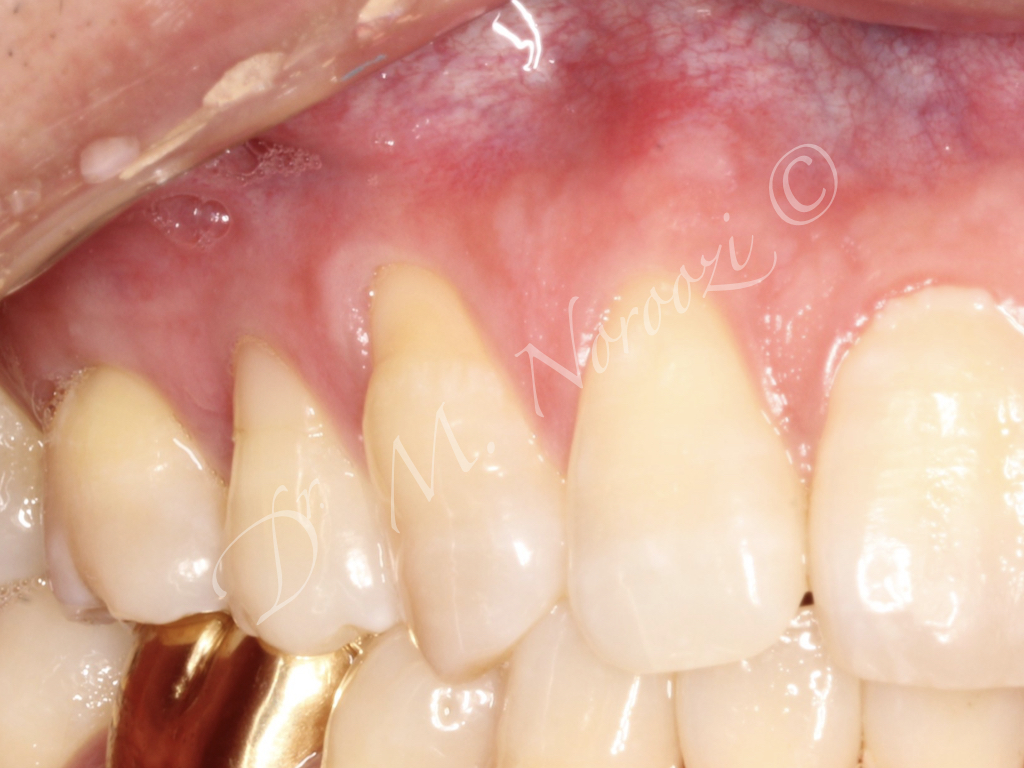

Connective Tissue Gingival Grafting for Gingival Recession